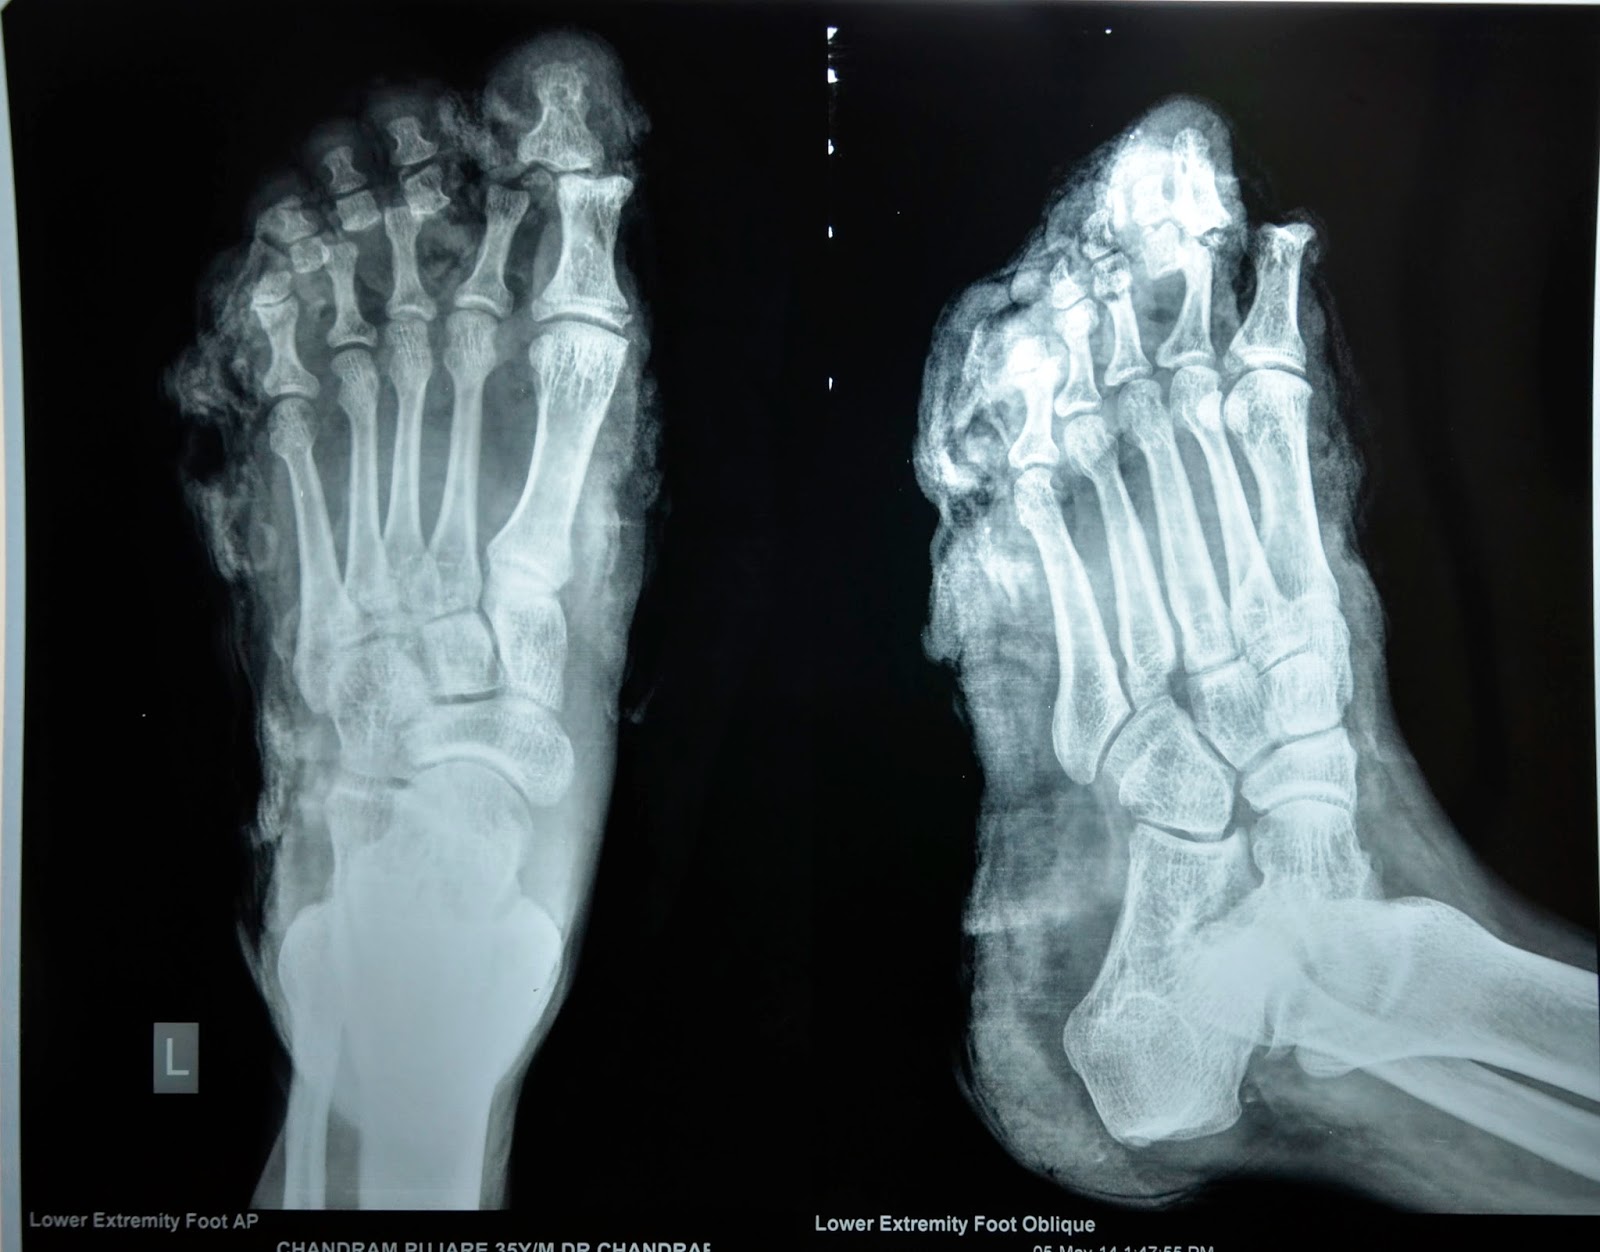

CRUSH INJURY FOOT MULTIPLE METATARSAL FRACTURE DEBRIDMENT , KWIRE Crushing Injury In Foot crush injuries demand immediate attention! a crush injury of the foot is a condition that occurs after the foot is compressed between two hard surfaces. foot crush injuries are more severe than regular foot fractures. a foot crush injury is a severe type of broken foot condition. crush injuries to the foot are a rare. Crushing Injury In Foot.